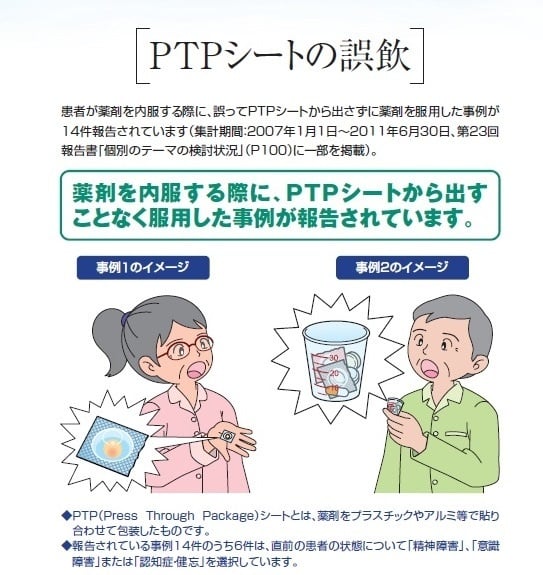

Https Www Kuhp Kyoto U Ac Jp Wwwrisk News Jyohou107 Pdf

食道にptpシート 内視鏡で除去も 医療機能評価機構 誤飲報告相次ぎ

Https Www Kuhp Kyoto U Ac Jp Wwwrisk News Jyohou107 Pdf